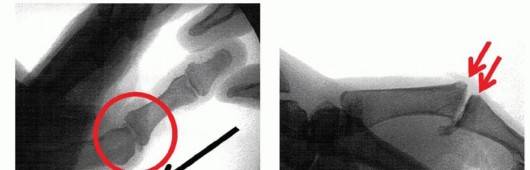

The physician should review all imaging studies. In most cases, those will be limited to plain radiographs and perhaps spot films from fluoroscopic evaluations.Films should be reviewed for any bony abnormalities, especially nondisplaced fractures. One should avoid fracture displacement during intraoperative manipulation of the thumb.In fracture-dislocations of the MP joint, larger fragments are stabilized using Kirschner wires or screws and smaller avulsion-type fragments are excised and the ligament is secured to the bone.For chronic cases, it is important to review the films and rule out osteoarthrosis, which would warrant different treatment strategies.Examination under anesthesia with the assistance of fluoroscopy can be useful to confirm the degree and direction of joint instability.Spot films obtained before and after surgical stabilization can be helpful visual aids for use in postoperative discussions with the patient and his or her family to explain again the nature of the problem and how it was treated.

TECH FIG 5 • Tension band wire technique of arthrodesis in AP (A) and lateral (B) projections. Note the presence of the two parallel Kirschner wires, bent over at ends, and the stainless steel wire figure-8 construct.